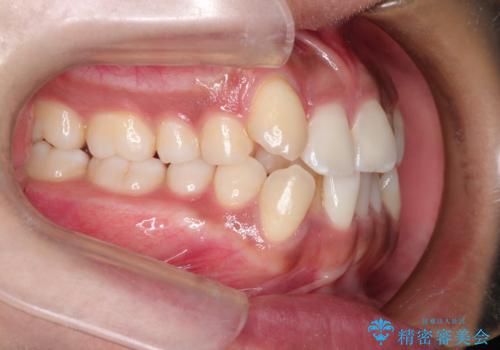

インビザラインと補助装置の併用による八重歯の抜歯矯正

- 八重歯を治したいとのことで来院されました。

重なりが強い右側の上下の歯を1本ずつ抜歯する計画としました。

インビザラインでの治療がご希望でしたが、右上の歯のかさなりが強いところは、補助装置である程度動かしてからインビザラインに移行することにしました。

下顎はインビザラインのみで治療を行いました。